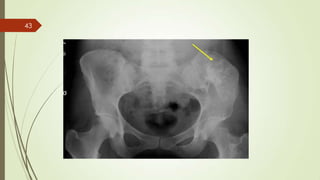

Imaging studies

 X ray : permeative lytic lesion with periosteal reaction.

33

34